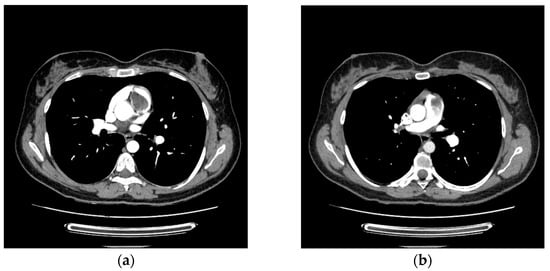

Primary cardiac tumors are rare, with an estimated incidence of 0.001% to 0.3% in autopsy series. Most are benign, the most common being cardiac myxomas, which typically originate in the left atrium. Right ventricular myxoma is among the rarest primary cardiac tumors, and its true incidence is difficult to determine, as most data come from isolated case reports. This paper aims to report a case of right ventricular myxoma in a young woman with a history of childhood malignancy and to discuss the possible association between the two conditions. Echocardiography, thoracic computed tomography (CT), and pulmonary CT angiography were used to assess the presence, location, and size of the tumor. The definitive diagnosis was established by histopathological examination. A 34-year-old woman, with a past medical history of acute lymphoblastic leukemia (ALL) in childhood, presented with a dry cough and exertional dyspnea persisting for three weeks. Transthoracic echocardiography revealed a mass located in the right ventricular outflow tract (RVOT), attached near the tricuspid valve and intermittently prolapsing into the pulmonary trunk. CT imaging confirmed the presence of the tumor in the RVOT and the main pulmonary artery. Because of the high risk of massive pulmonary embolism, the patient underwent urgent surgical excision of the tumor. Histopathological analysis confirmed the diagnosis of cardiac myxoma. The postoperative recovery was uneventful, and the three-month follow-up showed no recurrence or signs of pulmonary embolism. The patient’s history of ALL raised the question of a possible association; however, a review of the literature revealed no previously reported link. In conclusion, right ventricular myxomas are extremely rare. The occurrence of cardiac myxoma in this patient following childhood ALL appears to be incidental. Further research is needed to determine whether ALL survivors have an increased predisposition to subsequent cardiac tumors. Full article